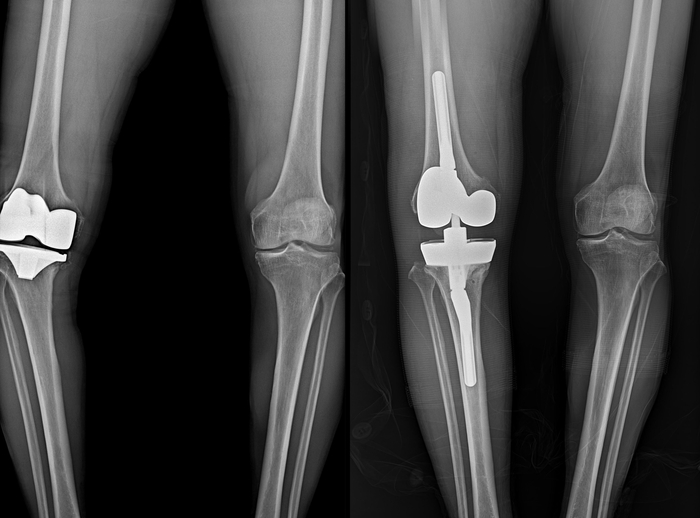

▲무릎 인공관절 수술 영상(왼쪽)과 재수술 영상. 사진=연세사랑병원

보건복지부 지정 관절전문 연세사랑병원이 개원 이래 무릎 인공관절 재치환술 1000례를 돌파하는 기록을 세웠다. 병원은 특히 최근10년 동안에만 833례의 인공관절 재치환술을 시행하며 국내에서 손꼽히는 재수술 경험을 보유한 의료기관으로 확인됐다.

그러나 평균 수명 증가에 따르는 인공관절 마모뿐 아니라 부정정렬, 인공관절 불안정성, 해리, 감염 등으로 인해 재수술이 필요한 경우는 여전히 존재한다. 문제는 재수술이 첫 수술보다 훨씬 복잡하고 고난도의 기술을 요구한다는 점이다. 병원의 자체 통계에 따르면 지난 10년간 무릎 인공관절 재수술을 받은 환자 833명 중 58%인 483명이 70대 이상의 고령이었다.